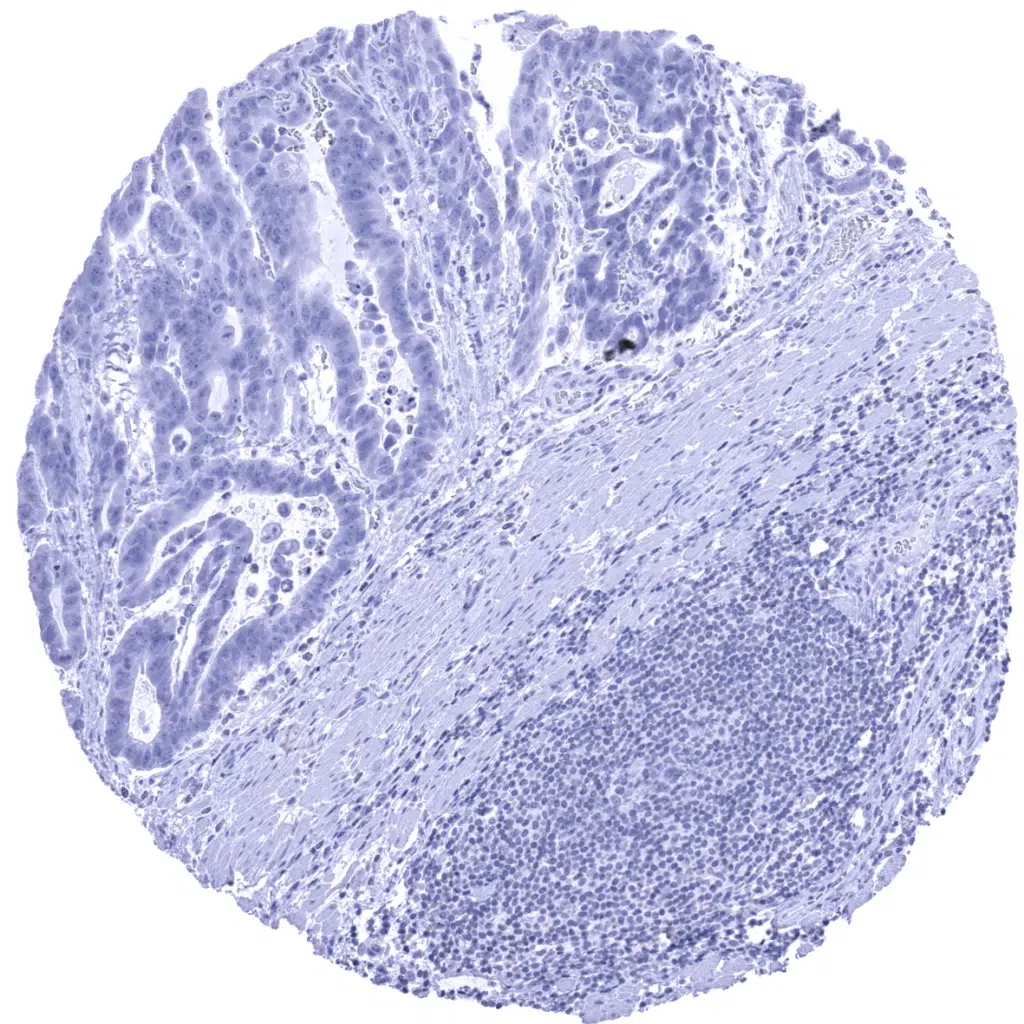

Pancreas - Elastase 3B negative ductal adenocarcinoma.